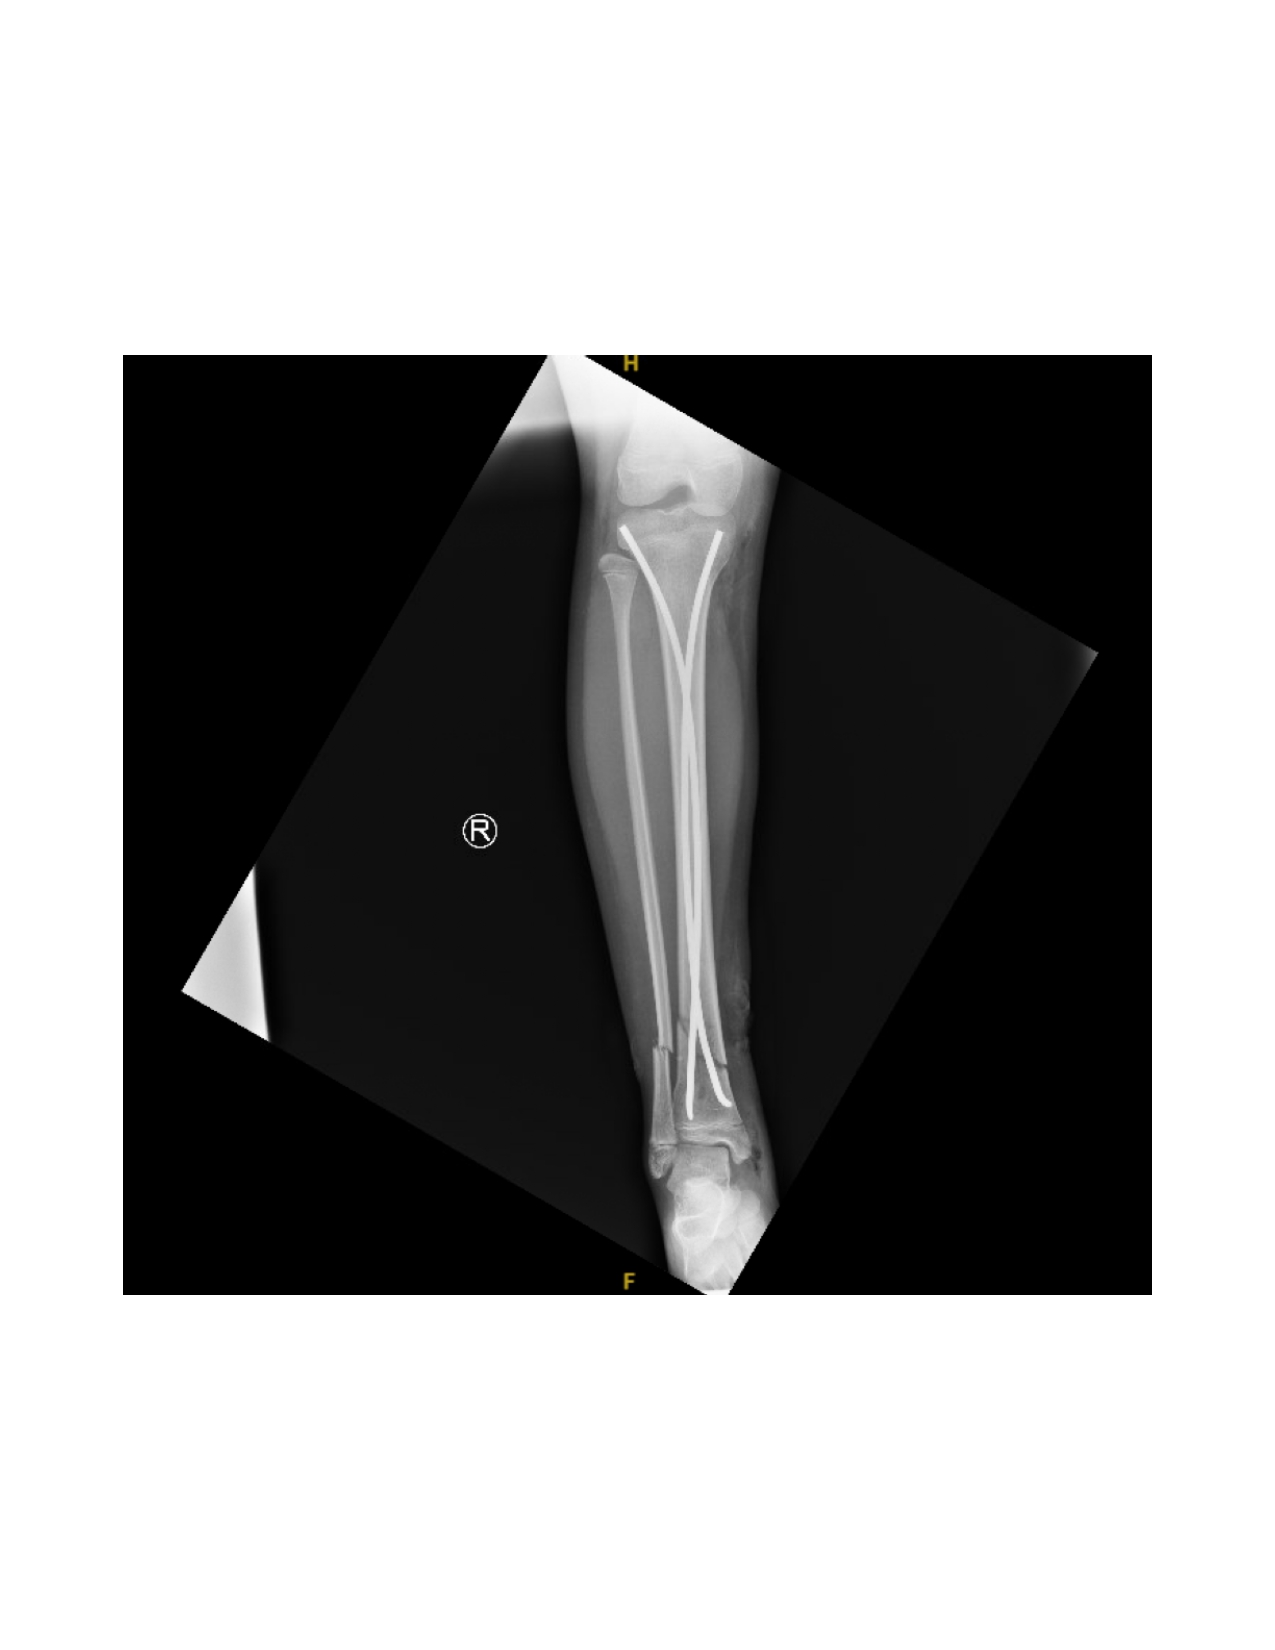

Next, the fracture is manually reduced and both nails are gently advanced past the fracture site by mallet. The curvature of the nails and their tips assists in reducing and stabilizing the fracture, inserted shy of the growth plate. Nail positioning is confirmed by fluoroscopy (Figure 5).

If displacement occurs after insertion, additional nail contouring may be necessary. To correct valgus angulation, the lateral nail can be rotated 180o medially. For procurvatum angulation, both nail tips are rotated 90o anteriorly without altering the medial and lateral orientations. For recurvatum deformity, both nail tips are directed posteriorly. Once a satisfactory reduction is achieved, the nails are hammered distally, preserving the distal physis (Figure 6).

The fracture site is then reassessed under fluoroscopy to confirm maintained reduction. (Figure 8 and Figure 9) Wounds are irrigated and closed in two layers, followed by sterile dressing and short leg splint application.